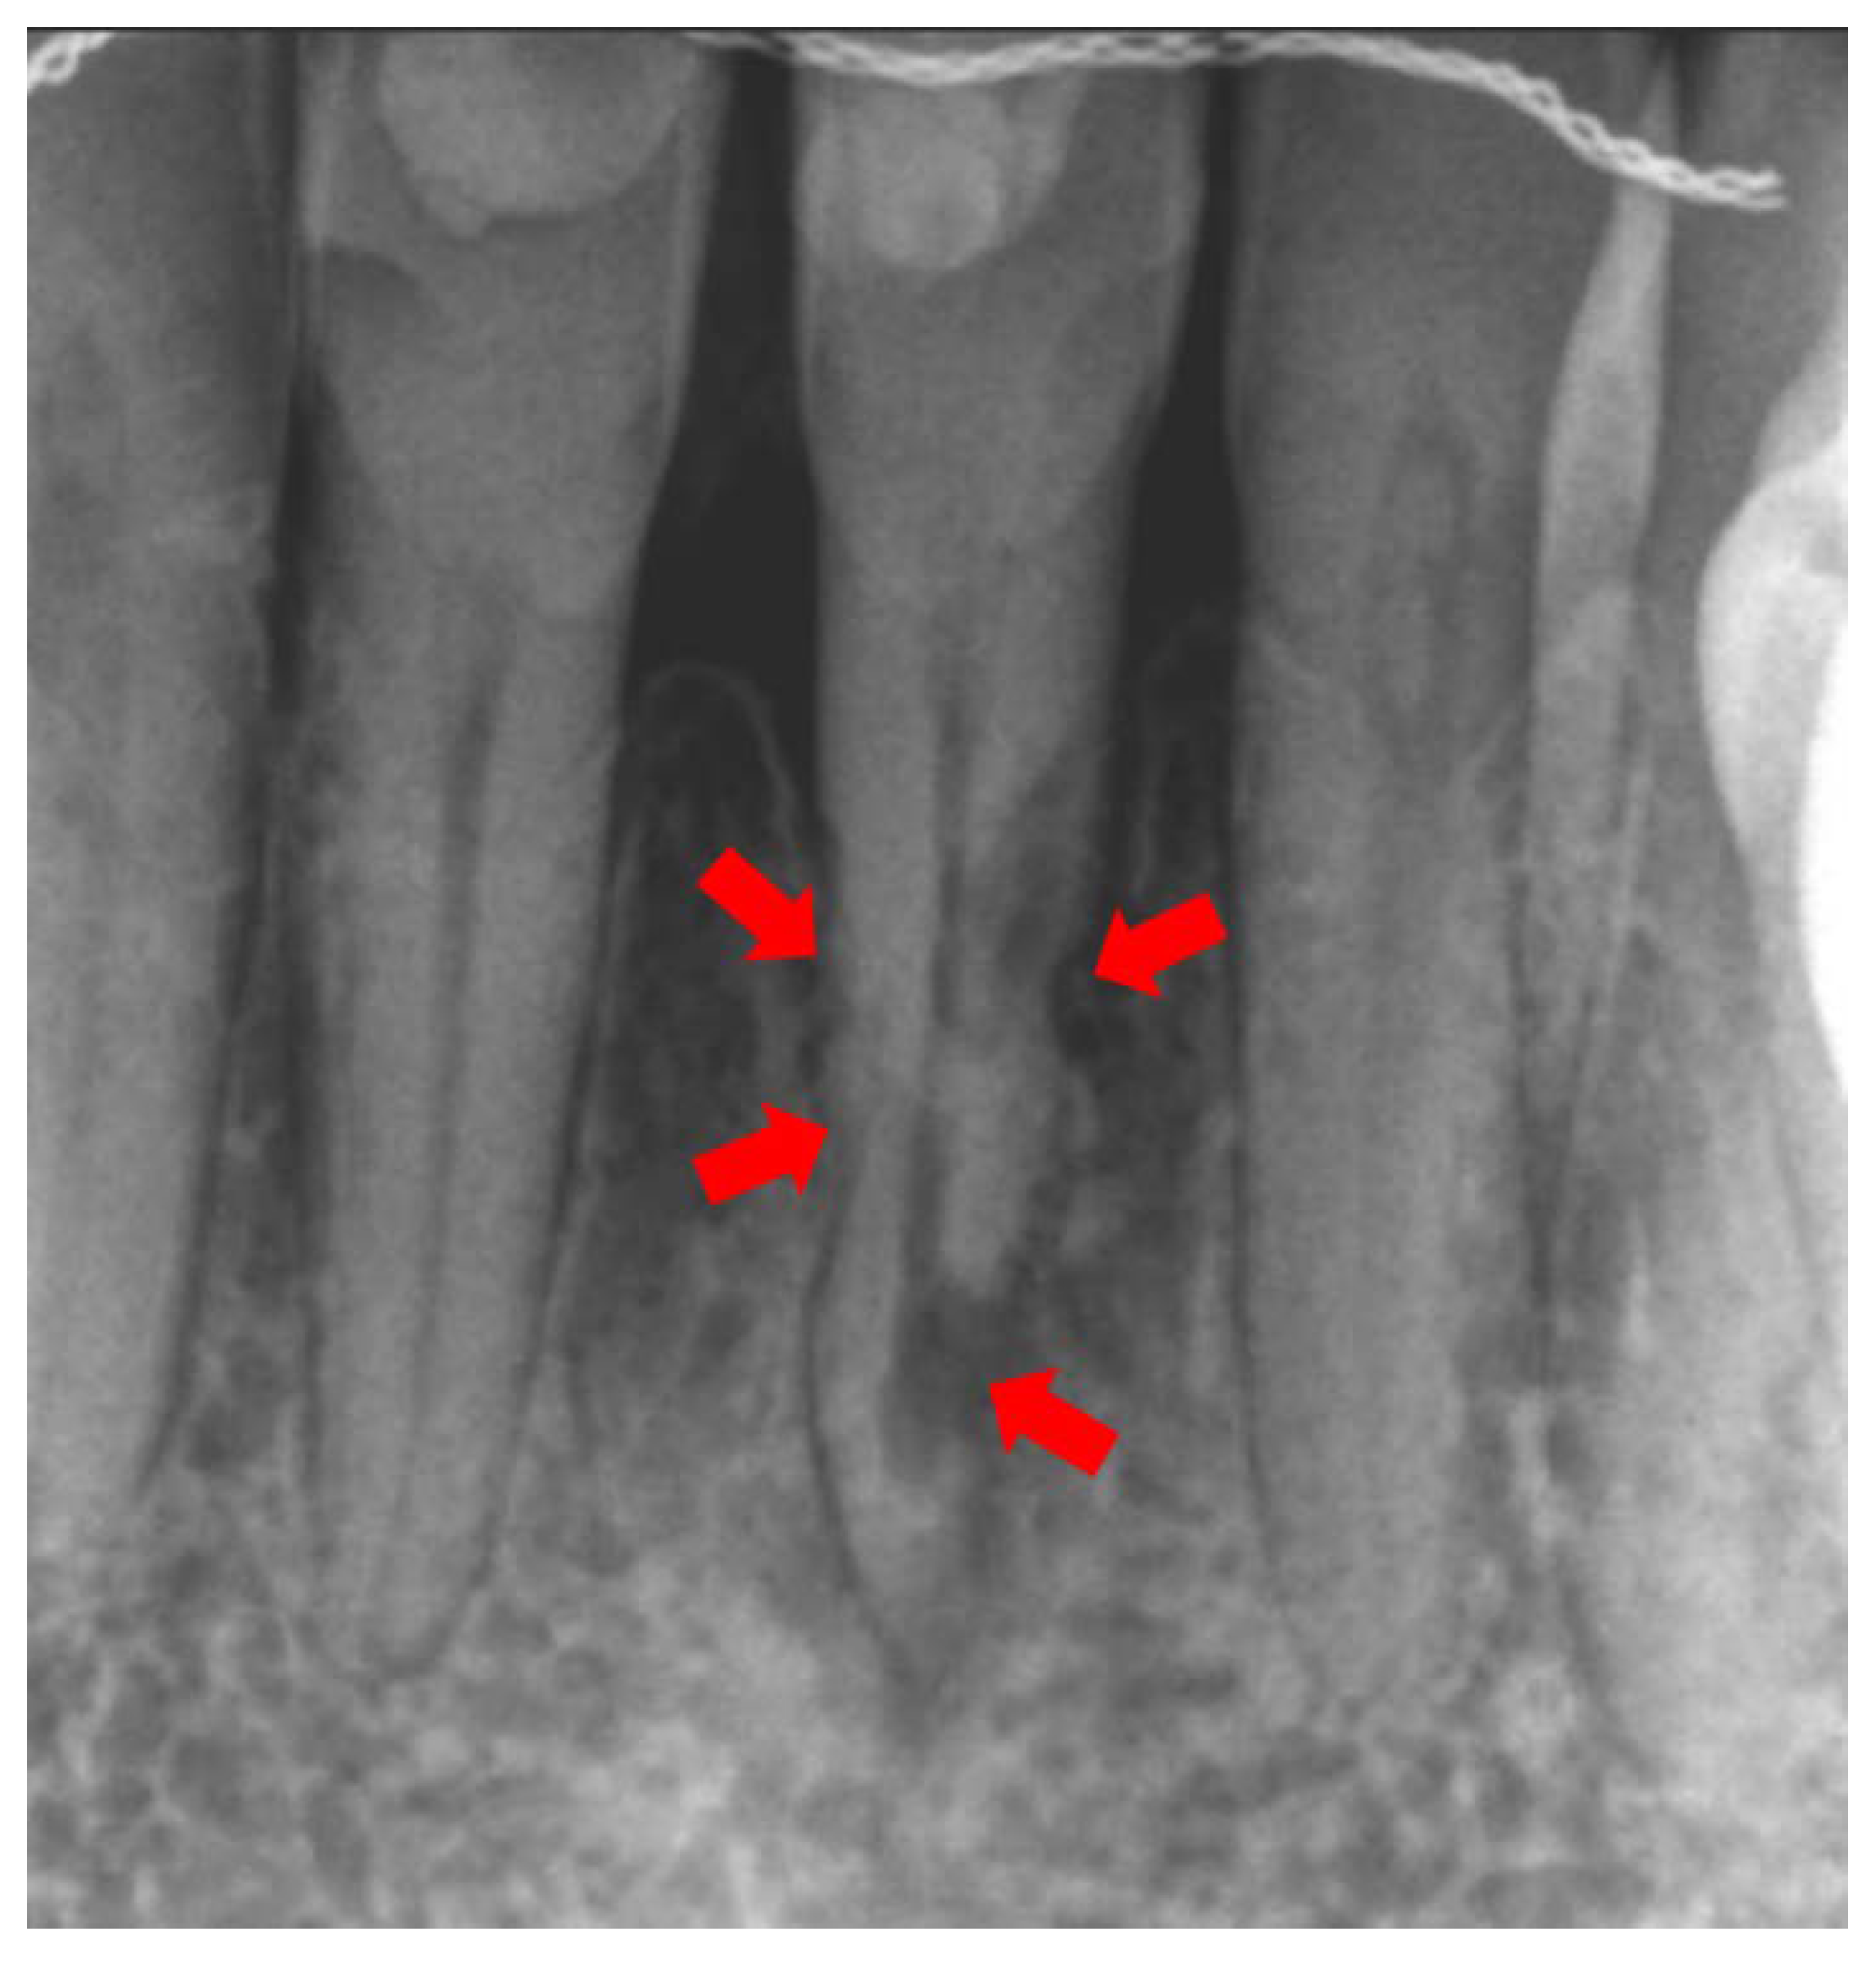

2. Etiology and Pathogenesis

3. Diagnosis